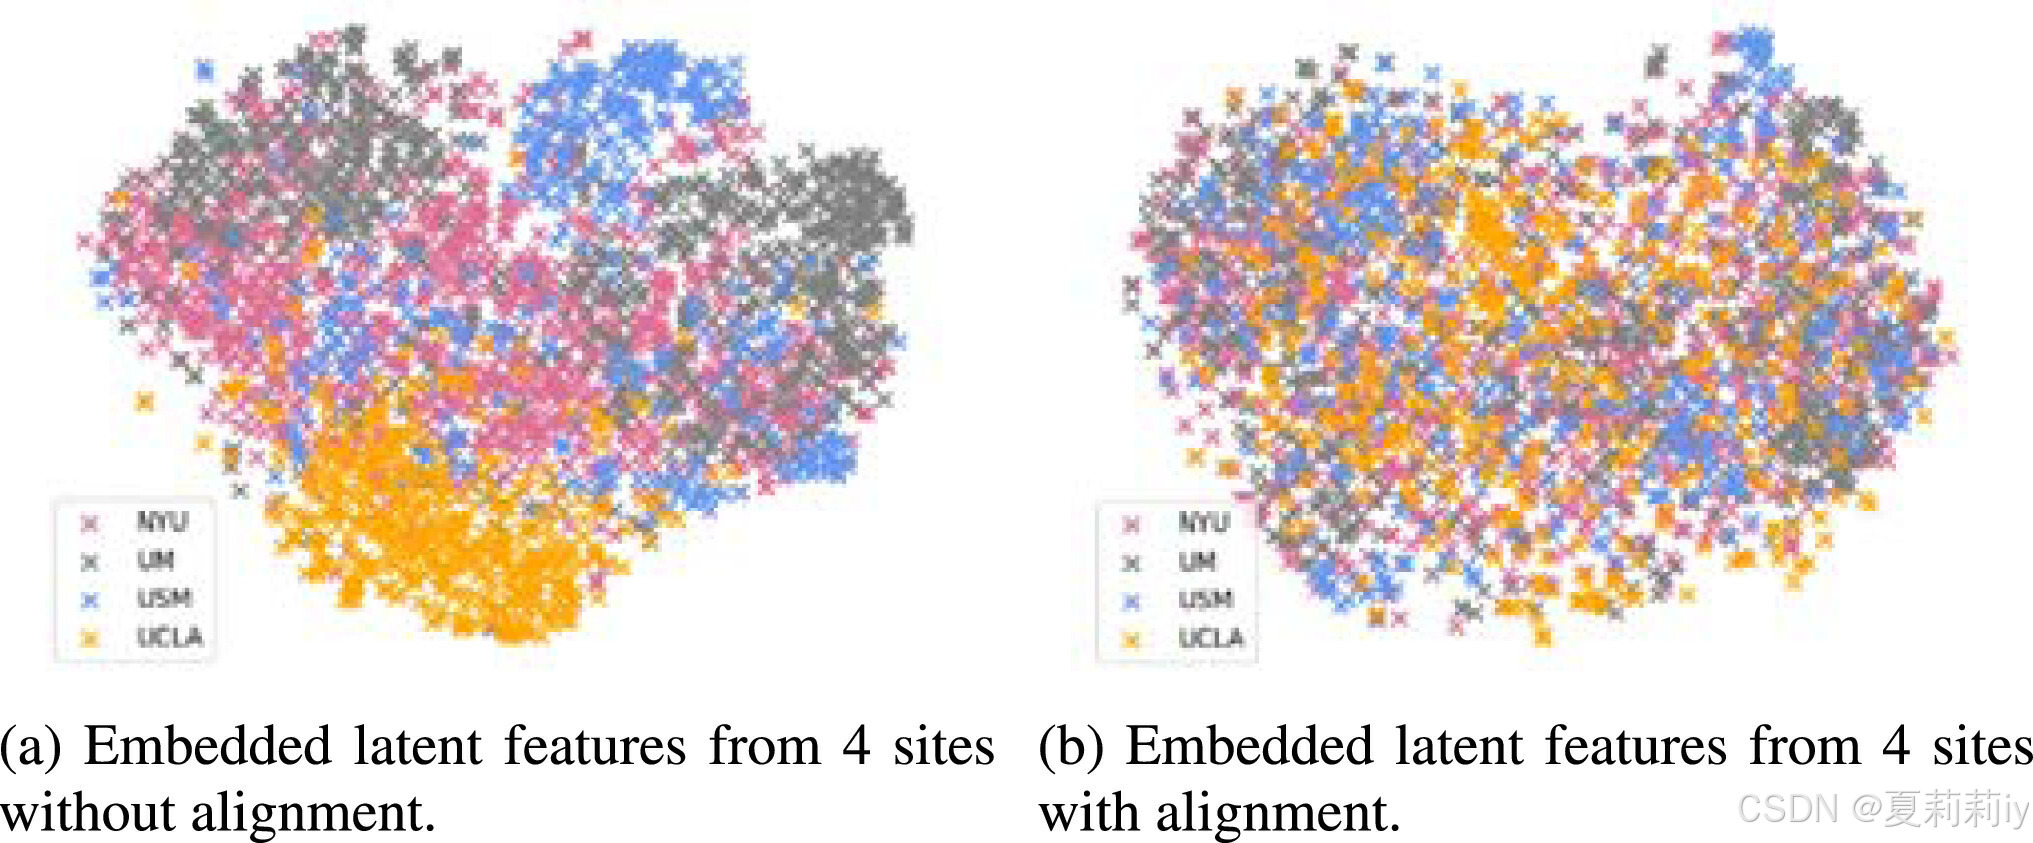

(1)Aligned feature embedding

①Visualizing fully connected layer embedding: